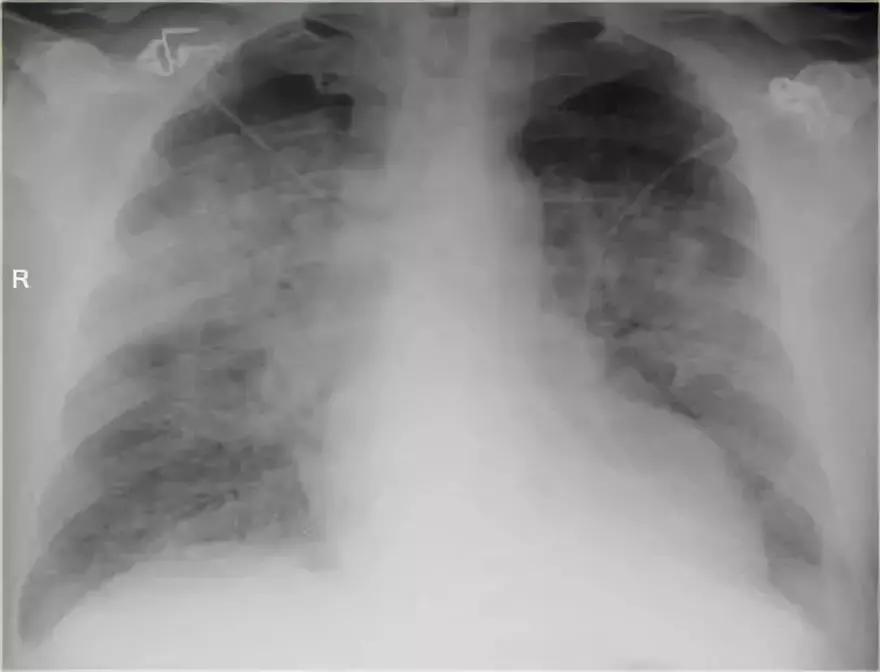

2.病例二

➢ 胸部X线显示,肺右上叶出现密度增加的模糊阴影,肺体积没有缩小

➢ 右肺门在正常的位置

➢ 箭头所示为空气-支气管征

➢ 结合适当的临床诊断,很像大叶或肺段性肺炎

➢ 然而,如果患者出现体重减轻,或症状时间持续较长,可能存在慢性实变的病因。

➢ 诊断结果为,肺炎链球菌引起的急性大叶性肺炎

图4 肺炎链球菌引起的急性大叶性肺炎